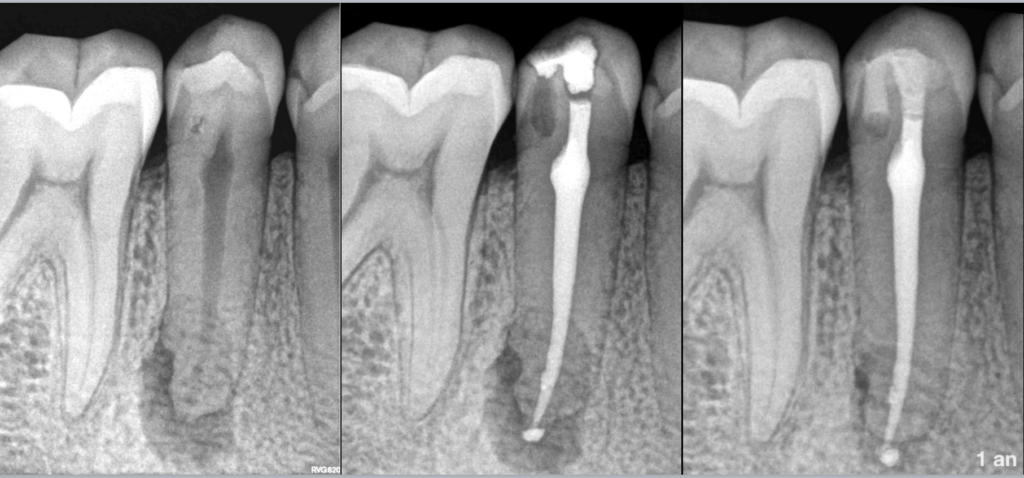

🦷 Pulpe nécrosée

🧐 Parodontite apicale asymptomatique

🌀 Dens invaginatus